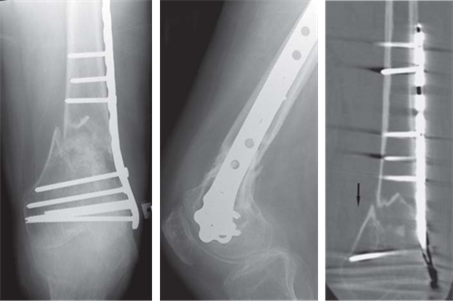

A B C

Reproduced from C. Bulstrode et al., Oxford Textbook of Trauma and Orthopaedics second edition, 2011, fi gure 1.10.6, p. 77, with permission from Oxford University Press.

This patient fractured a femur 4 months ago, but is still getting significant pain. What do you see and how would you manage it?

This patient fractured a femur 4 months ago, but is still getting signifi cant pain; what do you see and how would you manage it?

This is an AP radiograph showing a supracondylar fracture treated with a locking plate device. The fracture doesn’t show any signs of healing and at 4 months’ post-fi xation this would be an established non-union.

First infection must be excluded as this can also cause non-union.

If not infected:

z Open debridement

z Bone graft (iliac crest graft) z Additional BMPs? z Fixation — repeat internal or external (Ilizarov)

What factors infl uence fracture healing?